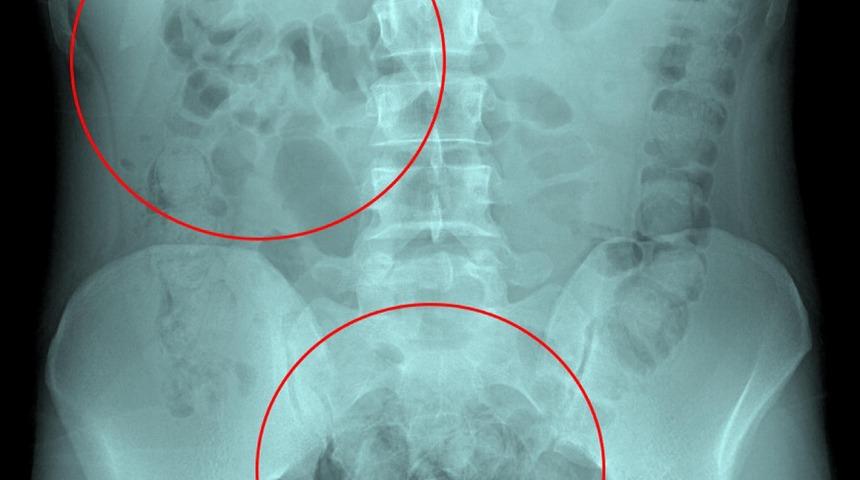

Tedavi altına alınan Narziveh'in çekilen röntgen filminde midesinde cisim tespit edildi. Ameliyata alınan Zarziveh'in midesinden 2'si patlamış 72 adet kapsül halinde uyuşturucu madde çıkarıldı.

Gördükleri manzara halinde şaşkına dönen doktorlar durumu polise bildirdi. Gelen polis ekiplerinin yaptığı incelemede 890 gram uyuşturucu maddenin metamfetamin olduğu belirlendi. Narziveh, 5 gün süren tedavisinin ardından Narkotik Mücadele Şube Müdürlüğü ekiplerince gözaltına alınarak emniyete götürüldü.